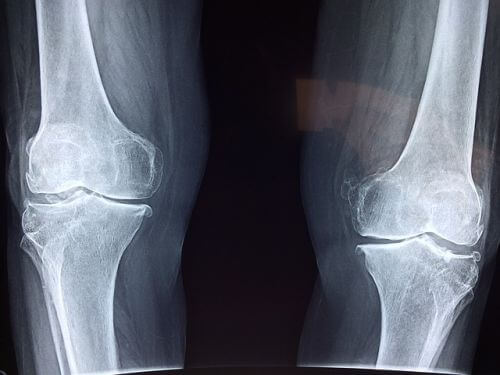

무릎관절염 KL grade상 3-4기에 해당되시는 환자분들은 인공관절 치환술이 필요합니다. 현재는 수술 재료도 좋아지고, 사람의 수명이 늘어나기 때문에 인공관절 치환술을 하신 분들을 쉽게 찾아볼 수 있는데요. 어떤 분들이 해야 하는지 정확히 말씀드리겠습니다.

XR상으로 말기 관절염이라도 통증이 극심하지 않은 환자는 일상생활에 큰 지장을 주지 않는 한 수술을 하지 않고 다른 방법으로 관리할 수 있다는 것을 꼭 기억해 주세요.